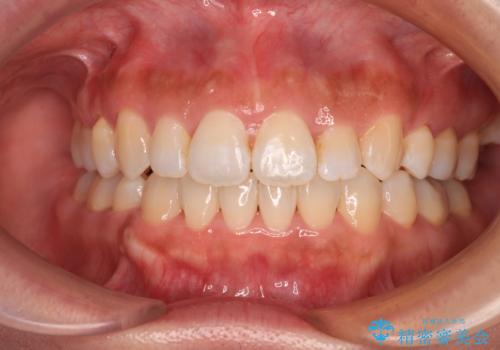

[ マウスピース矯正 ] 出っ歯に見える前歯を改善したい

![[ マウスピース矯正 ] 出っ歯に見える前歯を改善したいの症例 治療後](https://seimitsushinbi.jp/wp/wp-content/uploads/2023/10/8a6c9bf89570c0c75da0a5fabd1cd70e-500x350.jpg?v=1697014858)